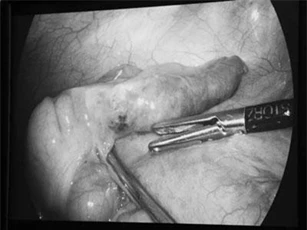

Viêm ruột thừa ở trẻ em là 1 bệnh lý khá phổ biến. Gần như tuần nào Bệnh viện Sản Nhi Ninh Bình cũng tiếp nhận và phẫu thuật cho 5 - 7 trường hợp viêm ruột thừa.

Với tiền sử 5 lần phẫu thuật ổ bụng, đến tuổi 70 cụ bà lại mắc bướu thận ở giai đoạn tiền ung thư. Cụ đã tránh được nguy cơ vướng các dải xơ dính, tổn thương nội tạng, tắc ruột, liệt ruột… nhờ robot phẫu thuật cắt bướu thận sau phúc mạc.

Cụ ông N.V.T. (97 tuổi, trú tại Nghi Yên, Nghi Lộc, Nghệ An) bị viêm phúc mạc do túi mật hoại tử, viêm ruột thừa thứ phát.